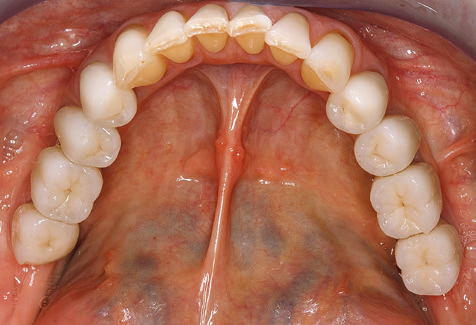

The ten-year check-up revealed no indications of advancing clinical attachment loss or peri-implant bone substance loss (Fig. 3).

The patient continues to visit the clinic every six months for SIT. In the following, the patient is taken as an example for demonstrating the individual working steps in a structured SPT session as it has been performed with barely any modifications over the last 12 years. Of course, some new materials and devices have been integrated into the concept over the years. This clinical case report presents the current material and device concept.

Standardised and regular risk-adapted care in the scope of SPT is the key to treatment success for the clinical long-term success in periodontically compromised patients. This is particularly true for patients fitted with implants following successfully completed periodontal treatment (Fig. 11a and b).